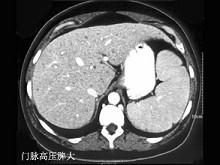

选项 A、脾脏脓肿 B、脾血管瘤 C、肝硬化并发脾肿大 D、某些血液疾病 E、外伤性脾破裂

答案 ABCDE